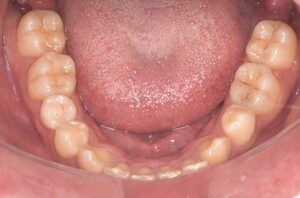

症例3

来院2回目、TBI後

症例

SRP後

初診時、TBI前

基本情報

年齢・性別 27歳・男性

主訴 主訴:左右下の歯ぐきに違和感がある

治療部位:全顎

治療内容 1.歯周基本検査、レントゲン撮影、口腔内写真、歯磨き指導、歯石除去、着色除去

2.SRP(スケーリングルートプレーニング)、再評価

その他

3.親知らずの抜歯

4.カリエス処置:右上1.2.3左上1.2.3右下6左下7CR(レジン充填)、右下7セラミックIn

5.定期検診

治療期間 6ヶ月

治療費 ※歯周基本治療の費用:PMTC以外保険診療3割負担

合計:19,680円

1.初診検査(歯周ポケット検査.レントゲン撮影):3,010円

2.歯磨き指導、歯面の歯石除去:1,410円

3.PMTC(自由診療):5,500円

4.SRP(歯周ポケット内の歯石除去)×4回:約2,000円/回

5.再評価:1,760円

(2023年12月現在)

リスク・副作用 ・最初は歯磨きをすると歯ぐきから出血するが毎日ホームケアを続けることで出血が徐々になくなる

・歯ぐきが腫れている状態が改善されると歯ぐきが引き締まり退縮するため、歯ぐきが下がったように感じることがある

・歯ぐきが引き締まると歯間が開いたように感じることがある

・歯ぐきが引き締まると知覚過敏の症状がでる可能性がある

・一度歯石を除去しても毎日のホームケアを怠ると再度歯石がつく

・治療後も再発を防ぐために定期的なメインテナンスが必要である

治療方針 1.初診検査(レントゲン撮影、口腔内写真、歯周検査、歯磨き指導)

2.歯磨きチェック、歯石除去、PMTC

3.SRP

4.再評価

特記事項 ・歯科医院は今回初めて

・タバコは24歳まで3年ほど吸っていたが健康のためにやめた

・親知らずは右下以外抜歯

・歯ブラシはルシェロP20M、補助用具はフロスを処方

担当者所見 全体的に歯と歯ぐきの境目に歯垢(細菌の塊)が残り、日々のホームケアで落とし切れていなかったことと、歯科医院への定期検診の習慣がなかったことから、全顎的な歯肉炎になってしまったと考えられる。

歯周基本治療とホームケアで歯ぐきの腫れや歯周ポケット、出血率などかなり改善されたが、出血がまだ0%ではない為、引き続き歯ブラシの当て方をお伝えしつつ今後は定期検診で3ヶ月おきに再発しないよう一緒に管理していく。